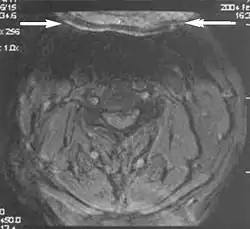

Fig. 6. Wrap-around artifacts.[1]

Fig. 7. Wrap-around artifacts.[1]

A wrap-around artifact also known as an aliasing artifact, is a result of mismapping of anatomy that lies outside the field of view but within the slice volume.[4] The selected field of view is smaller than the size of the imaged object. The anatomy is usually displaced to the opposite side of the image (Figs 6 and 7). It can be caused by non-linear gradients or by undersampling of the frequencies contained within the return signal.[1] The sampling rate must be twice the maximal frequency that occurs in the object (Nyquist sampling limit). If not, the Fourier transform will assign very low values to the frequency signals greater than the Nyquist limit. These frequencies will then ‘wrap around’ to the opposite side of the image, masquerading as low-frequency signals. In the frequency encode direction a filter can be applied to the acquired signal to eliminate frequencies greater than the Nyquist frequency. In the phase encode direction, artifacts can be reduced by an increasing number of phase encode steps (increased image time). For correction, a larger field of view may be chosen.[1]